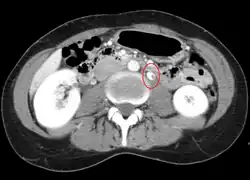

Thrombosis in the left renal vein associated with dilation